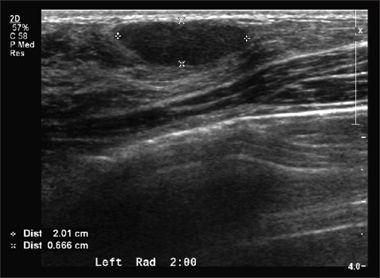

THE CASE: A 16-year-old girl has had a left breast lump for 6 months that recently became tender. Except for several small nodules in both breasts and tenderness of the lateral left breast, physical findings are normal and the patient is otherwise healthy. The mother is highly concerned that her daughter has breast cancer because her maternal grandmother died of the disease. A sonogram of the left breast is shown.

The ultrasonographic finding of a well-defined, hypoechoic, homogeneous, oval mass measuring about 20 to 30 mm in diameter (in this case, 16 × 20 × 7 mm) is consistent with a fibroadenoma.1 This benign neoplasm is the most common cause of an adolescent breast mass. In various studies, fibroadenomas account for about 60% to 90% of breast tumors diagnosed either surgically or sonographically in adolescents.2-5